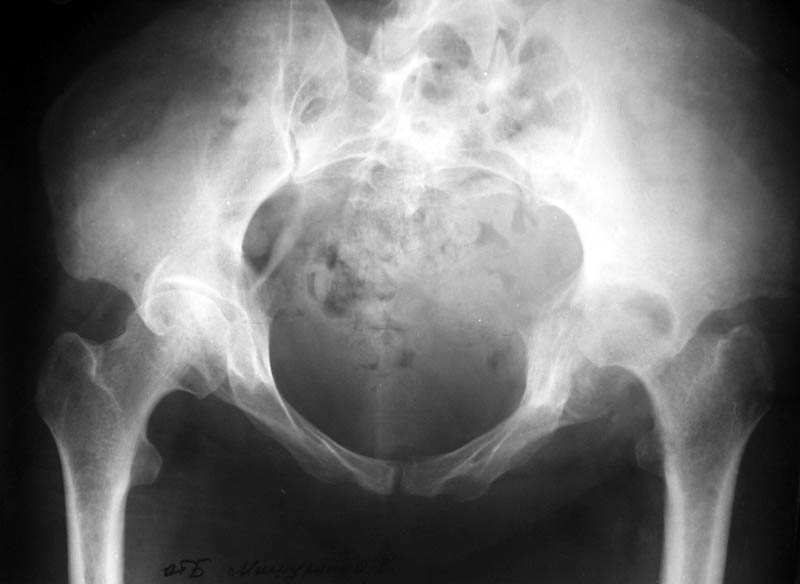

Женщина, 45 лет. В марте перенесла левосторонний коксит неизвестной этиологии. Специфику и онкологию исключили.

Интраартикулярных инъекций не было. Сейчас процесс клинически и рентгенологически - стабилизировался. Состояние вполне удовлетворительное.Предполагается тотальное эндопротезирование с пластикой полости аутокостью. Возможна ли бесцементная <чашка>? Заранее благодарю! С уважением,А.В.Владзимирский

Дополнение - проконсультировался с женой-она специалист рентгенолог - на КТ большое колиество мягкотканного компонента - ищите микоплазмы или бруцеллу. Я склоняюсь к виопсии.

Пртезирование через пол года после коксита закончившегося лизисом сустава, который на снимках выглядит как гнойный? Что значит неизвестной этиологии?

Уважаемый коллега! Последняя версия - мы пролистали ренгенологическую книженцию-так картинка вполне подходит под сустав Шарко (neuropatic joint ). В тазобедренном суставе патология редкая (но меткая). Ищите причину - варианты - нейросифилис, сирингомиелия, опухи спинного мозга (и выше тоже) компрессия спинного

мозга извне, рассеяный склероз, алкоголизм. А так-же : склеродерма ,Рейно,ревматоидный артрит, амилоидная инфильтрация нервов,и это не считая всяких менингеомиелоцеле,asymbolia,Riley-Day syndrom,и все возможные другие нейропатии. На данном этапе не спешите оперировать(протезирование протиопоказано при нейропатических суставах),проконсультируйтесь с классным невропатологом,сделайте МЯР головного озга и